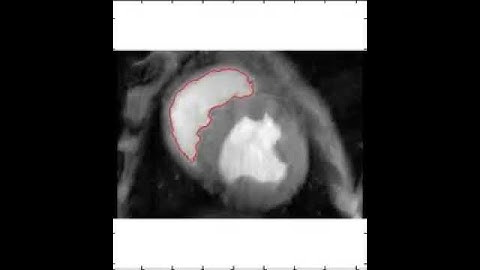

MODIFIED CHAN-VESE METHOD WITH HINTS FROM RANDOM WALK